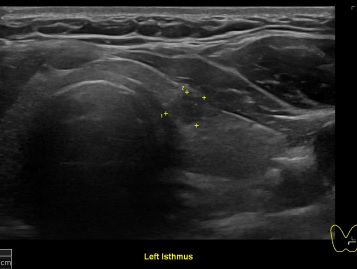

상기환자 외부검사이상소견 세침검사위해  내원하신 30대 중반 여성분으로 갑상선 초음파 시행후 의심스러운 갑상선 좌엽 결절 세포검사 진행후 갑상선암으로 진단되었습니다